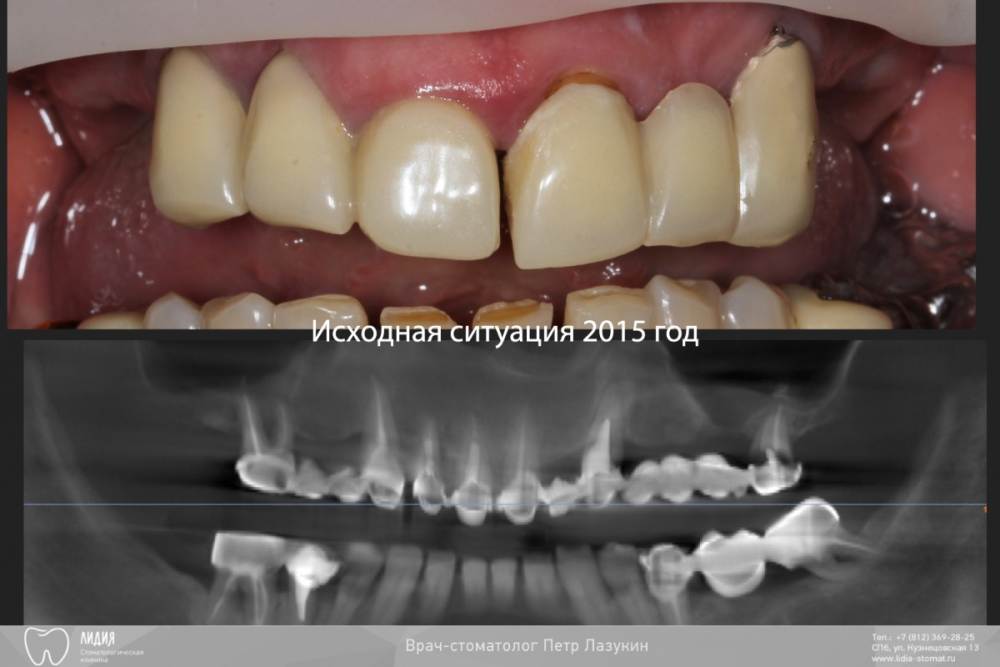

pit Опубликовано 5 октября, 2021 Поделиться Опубликовано 5 октября, 2021 Клинический случай. Старт работ в 2015 году. План простой: Полная дуга, верхняя челюсть. Начали в 2015, закончили в 2021. Какой был план? Зубы в/ч все под удаление. Фронт был временно сохранен для временного протезирования. Установлены импланты с костнопластическими манипуляциями. В качестве временных коронок использованы металлокерамические коронки. Следующим этапом, после интеграции, было открытие имплантов и изготовление временных коронок. И тут пациент пропал на 2 года, а затем еще на четыре)))). Лишь поломка времянок, через 6 лет, сподвигла пациента обратиться за изготовлением постоянных коронок. Протокол и комменты в слайдах. КТ после протезирования. 11.mov 1 2 2 Ссылка на комментарий